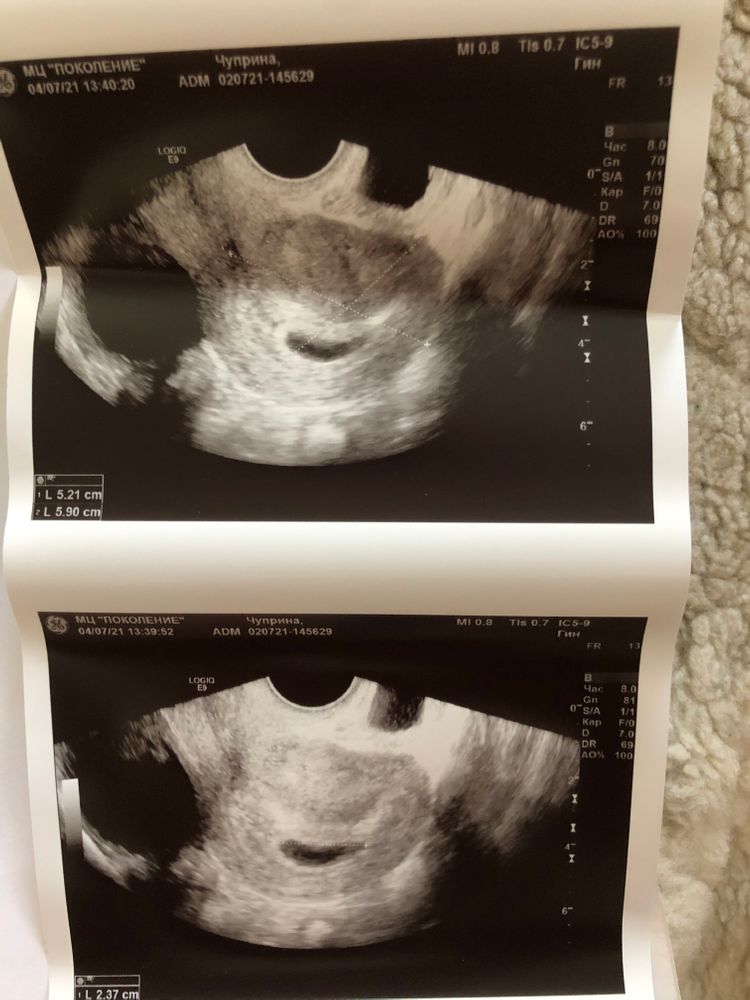

квитка, да,на вашем снимке если правильно разобралась,вот он похоже Изображение

Марина, желточный мешок на узи выглядит, как белое колечко.

Марина, Изображение

Olesya , я знаю как выглядит,у автора фото нечёткое,если увеличить похоже на колечко